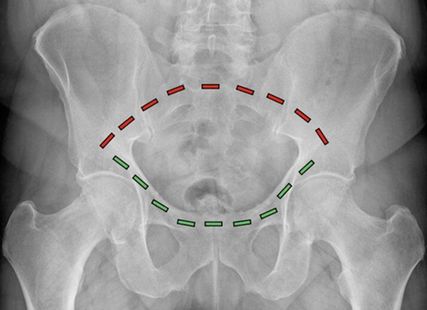

Abb. 1: Der Beckenring besteht aus einem vorderen (grüne Striche) und einem hinteren (rote Striche) Anteil. Während der vordere Beckenring durch die Schambeine gebildet wird, besteht der hintere Beckenring aus dem Kreuzbein und den Darmbeinen

FFP-Frakturen des geriatrischen Patienten entstehen im Gegensatz zu Beckenfrakturen des adulten Patienten als Folge eines niedrigenergetischen Traumas. Aufgrund der reduzierten Knochenqualität reichen also geringe Energiemengen aus, um das osteoporotisch veränderte Becken zu brechen. Für das Verständnis der Architektur des Beckens ist es entscheidend zu wissen, dass das Becken aus einer zusammengesetzten Ringkonstruktion besteht, wobei ein vorderer und ein hinterer Beckenring unterschieden werden (Abb. 1). Aufgrund des Kraftflusses, der aus dem Bein hauptsächlich über den hinteren Beckenring in den Rumpf verteilt wird, ist der hintere Beckenring für die Gesamtstabilität des knöchernen Beckens von primärer Bedeutung. Die FFP-Klassifikation gibt hier anhand der Beteiligung der unterschiedlichen Anteile des Beckenringes den gegenwärtig vollständigsten Überblick.1 In Abhängigkeit davon, ob es sich um ein- oder beidseitige Verletzungen des vorderen, des hinteren oder beider Beckenringe handelt, unterteilt diese Klassifikation in aufsteigendem Schweregrad die Verletzungsausprägung. Der Fokus der Behandlung der FFP-Frakturen liegt ebenso wie auch bei der Behandlung der Beckenverletzungen des Erwachsenen auf der Stabilisierung des hinteren Beckenringes. Im Gegensatz zu den Beckenringfrakturen des Erwachsenen, deren Entstehung eine hohe Verletzungsenergie und damit verbundene, lebensbedrohliche Begleitverletzungen wie Blutungen beinhalten, stehen bei den FFP-Frakturen aufgrund der niedrigen Verletzungsenergie die Schmerzbehandlung und die zügige Mobilisierung des Patienten im Vordergrund. Als ursächliche Mechanismen der Entstehung einer FFP-Verletzung gelten Stürze im häuslichen Umfeld bei geringer Fallhöhe und niedriger Aufprallenergie.